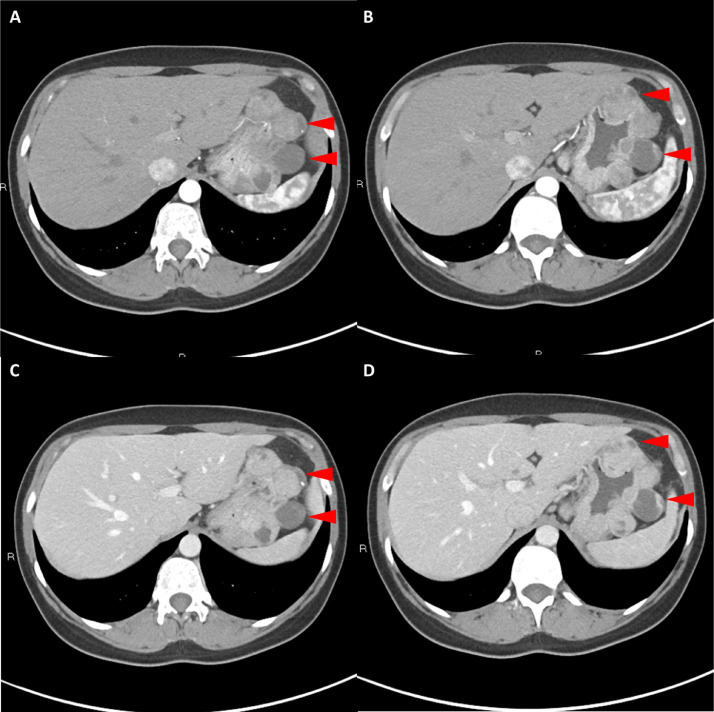

胸部、腹部和骨盆的对比增强动脉和静脉期 CT 显示多个圆形、主要是血管丰富的异质肿块,具有囊性和实性成分,起源于胃底和胃体(图 2-4)。 病变部分呈外生结构,被认为位于粘膜下层。 在颈部多发同步性副神经节瘤的情况下,最初的鉴别诊断包括多发性副神经节瘤、多发性 GIST 以及转移性疾病。

图 4: 胃肠道间质瘤的三维表示。 (A 和 B)胃肠道间质瘤在动脉期和冠状面的 3D 可视化提供了进一步的解剖细节和空间信息。